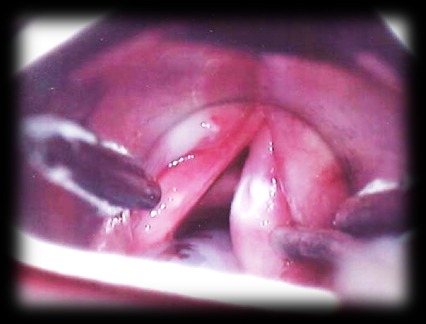

Лейкоплакия